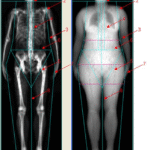

हड्डियों के लिए DEXA स्कैन.

DEXA scan for bones.

फुट स्कैन

Foot scan

किडनी की बीमारी का जल्द पता लगाने के लिए नेफ्रोपैथी स्क्रीनिंग

Nephropathy screening for early detection of kidney disease

धमनी संकुचन (PAD) के लिए वैस्कुलर डॉपलर

Vascular doppler for arterial narrowing (PAD)